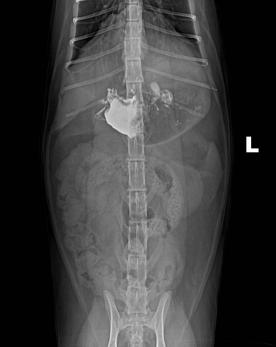

c.X线检查。针对阻线性较强的物质(如金属、骨头)较容易辨别,针对阻线性与组织密度相似的物体较难确定,但是可以通过消化道灌服造影剂判断是否有阻塞或可包裹物体。

机械性肠梗阻的读片要点:1.体积增大;2.形态轮廓变化;3.影像密度变化;4.浆膜细节变化。

金毛 线性异物